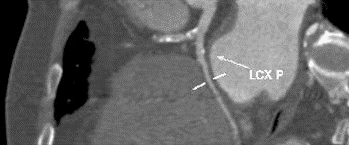

四、CT评估

1.术前冠状动脉影像学评估:冠状动脉轻度粥样硬化累及多支,前降支中度狭窄,回旋支及右冠轻度狭窄。

2.术前瓣膜CT测量:A .瓣环测量; B.瓦氏窦测量;C.窦管交接区测量;D.左室流出道测量;E.升主动脉(最宽处)测量;F.虚拟瓣叶形态,钙化分布。

患者为三叶瓣,瓣叶增厚,极重度钙化,左冠窦可见柱状钙化延申至流出道,双冠脉风险高度尚可,瓣叶未见冗长,考虑冠脉风险较低,心脏角度约68°,呈横位+升主扩张,预备上Snare;收缩期左室测值较小且流出道短径约16.8mm,选择20球囊预扩,预装L26 Venus-A瓣膜。